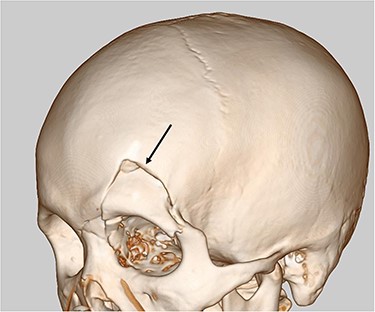

Our case was a 22-year-old man measuring 180 cm in height and weighing 86 kg. Two hours after eating a large amount of food, he was involved in a collision between his motorcycle and a motor vehicle. At the examination, he was alert and his vital signs were stable. The patient presented with an open skull fracture on the left forehead and described muscular defense throughout the abdomen. A whole-body computed tomography (CT) scan showed an open skull fracture reaching the left skull base (Fig. 1), and free air, ascites fluid, disruption of the gastric wall and a large amount of food residue behind the spleen (Fig. 2 and b). The head wound was first treated, and then, a laparotomy was performed on suspicion of a traumatic gastric rupture.

Head CT scan revealed open skull fracture reaching the left skull base (arrow) and mild brain contusion.